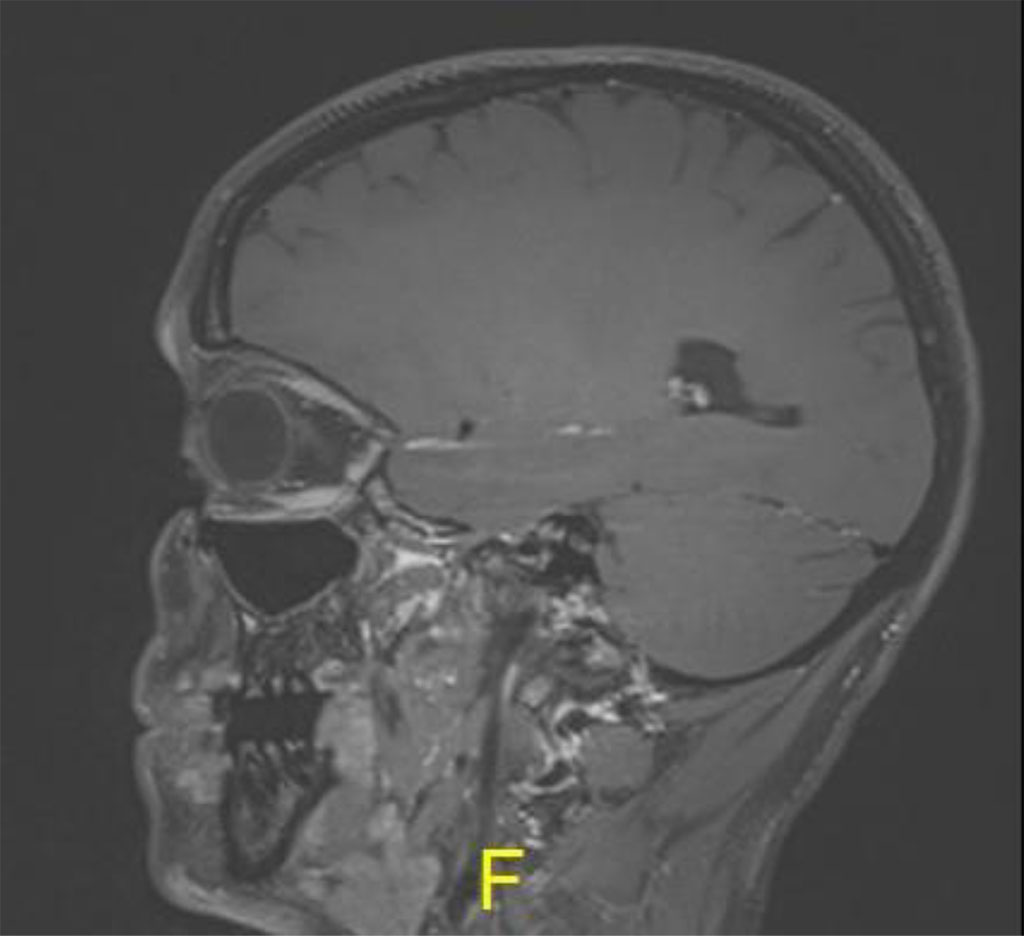

Following the procedure, the patient complained of diplopia in primary position with restriction of upgaze. The patient was treated with oral steroids with no improvement. MRI was 2 months post procedure, there was excellent anatomical improvement, with significant decrease of the lesion but with enlargement of the inferior rectus (Figures 4 a,b,c).

Figure 4b: Sagital MR T1: demonstrating thickening of inferior rectus in left